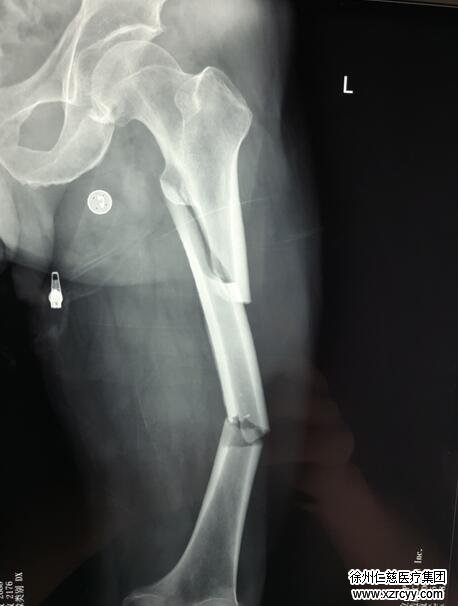

由于找不到老人亲属, 医院按照“三无病号”开通绿色通道,当即为老人实施了急诊手术。术中探查发现老人双股骨多发性骨折、胫腓骨闭合性骨折、开放性胫骨骨折,腓骨骨折并伴有头部血肿、肺挫伤、腰部软组织损伤,考虑到伤者年岁已高,医生为伤者先行清创缝合,肌肉修复和骨牵引术,手术后送至重症监护室,密切观察生命体征。

待老人的生命体征达到最佳手术状态后,2月24日和3月1日,关节外科主任蒋守海和主治医师邱东新分两次为老人进行了微创骨折复位固定手术,经过十余天的术后观察,目前老人已经脱离了生命危险,恢复状况良好。